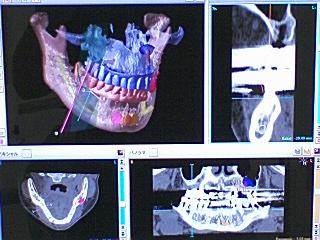

本日は、お昼休みを利用してアイキャットの営業の方と 近々インプラントオペを予定している患者様 3名の画像解析やサージカルガイド設計の打ち合わせなどをしておりました。

下顎奥歯の骨が少ないケースは、最も慎重さが求められます。ミリ単位で正確なインプラント体埋入が要求されますので 3次元画像解析によって骨質や神経、血管の走行位置を確実に把握する必要があります。

また サージカルガイドと呼ばれる ドリルの誘導路模型を作製したり、サージカルドリルを作製して可能な限り 誤差の無いオペをする必要があります。

3次元画像解析

CT 撮影や画像解析、サージカルガイド作製は 追加費用が掛かりますので なかなか患者様にもお願いし辛いのですが、安全、且つ 正確なオペの為に 是非ともご利用して頂ければと思っております。